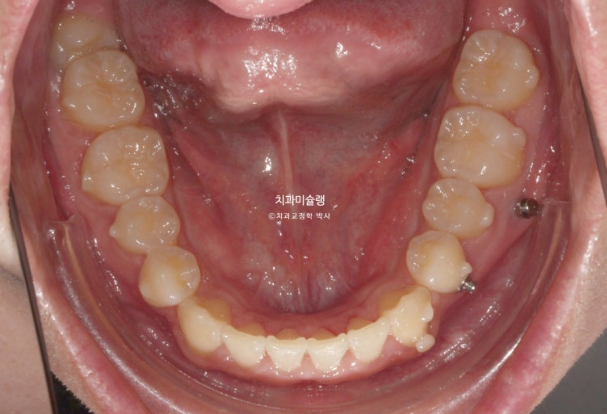

24.11

위 아래 중심선은 정확히 맞고

어금니 교합관계도 1급 입니다.

모든게 좋지만 환자분의 요구사항도 있었고 완성도를 위해 재제작을 1회 더했습니다.

11개 추가장치를 모두 낀 후 25년 6월 치료를 마무리 합니다.

이제 왜소치 무삭제 라미네이트가 들어갈 차례 입니다.

왜소치 라미네이트는 주변치아 색깔에 어울리도록 맞추는 것이 좋습니다.

자연스럽게 잘 치료가 되었습니다.

총 치료기간은 2년 6개월 재제작은 2회 했습니다.

어금니 교합은 좋고 1급 교합관계를 보입니다.